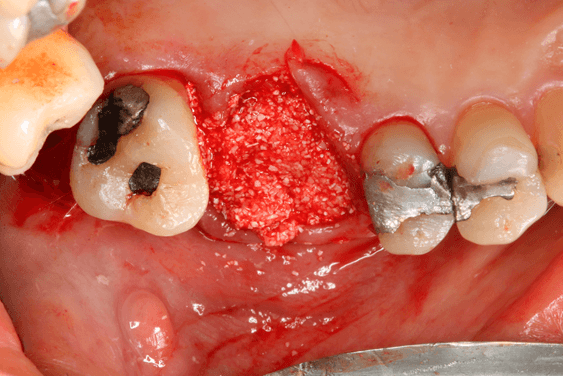

Avaliamos o desempenho do biomaterial de hidroxiapatita com colágeno tipo I (Extra Graft XG-13®) na manutenção do volume alveolar.

A aplicação como o caso clínico abaixo se mostrou uma técnica acessível a todos cirurgiões dentistas, pois se trata de um procedimento de simples execução e acessível. Logo, deveria constar na clínica diária.